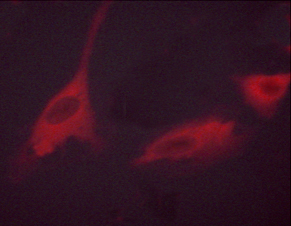

IHC (Immunohiostchemistry)

(Immunohistochemical analysis of paraffin-embedded Human Breast Carcinoma Tissue using P70 S6 Kinase Mouse mAb diluted at 1:200.)